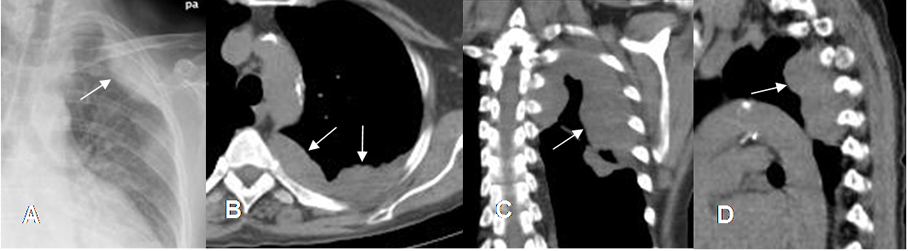

Fig 39 A. Mesotelioma.

A: Rx PA. Imagen de localización extra-pleural, en el tercio superior del hemitórax izquierdo.

B: TAC axial, C: TAC reconstrucción coronal y D: TAC reconstrucción sagital. Imagen de contornos bien definidos y lobulados.

Fig 39 B. Mesotelioma.